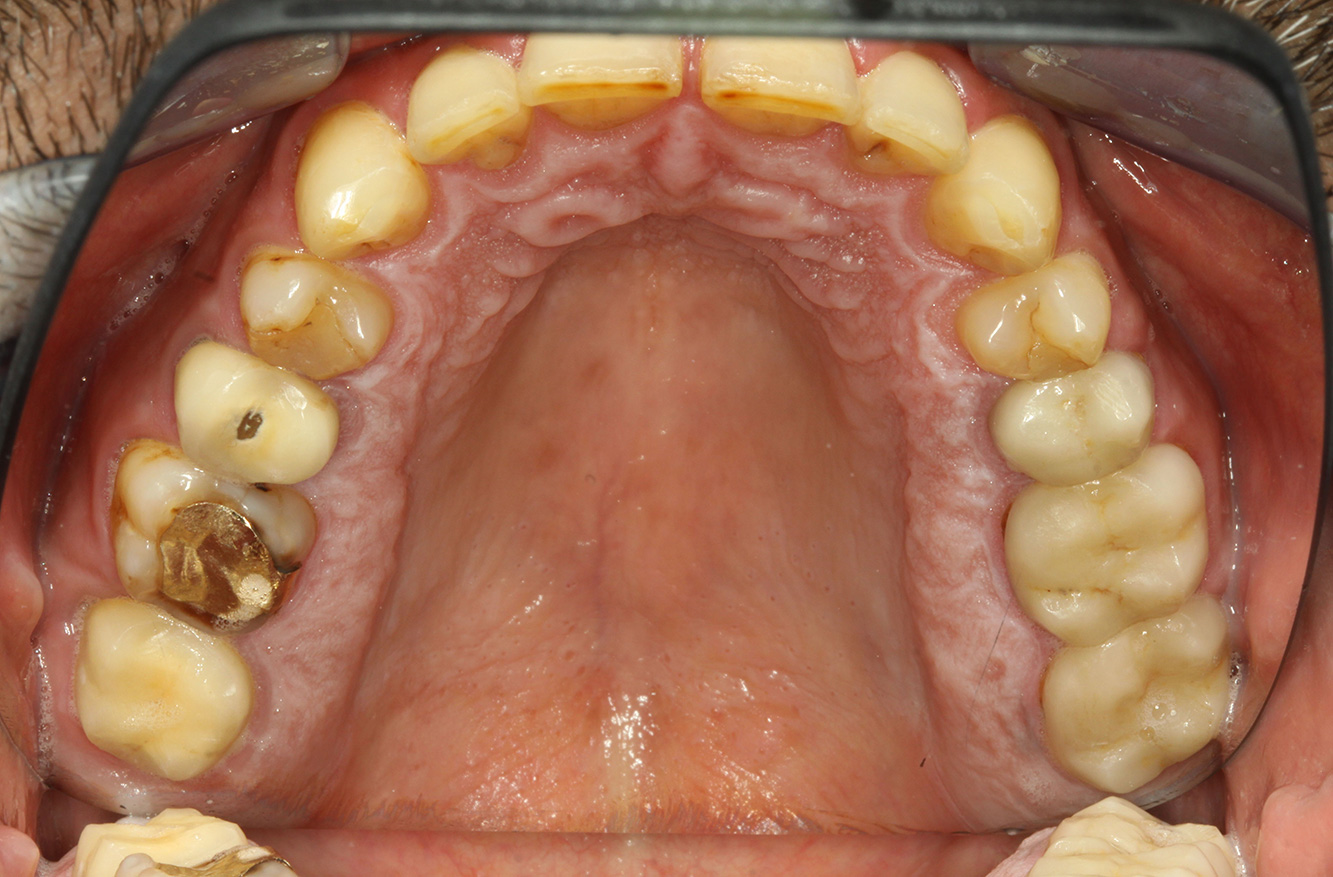

El paciente tiene 39 años con valvuloplastia frente a una insuficiencia valvular y endocarditis. Toma regularmente ASS 100 (ácido acetil salicílico) como anticoagulante. En el ámbito del estilo de vida, la alimentación se identifica como promotora de caries, ya que suele consumir alimentos azucarados y seis o siete comidas al día. La salud oral del paciente muestra un riesgo medio de caries con lesiones activas. El riesgo de periodontitis es bajo, presenta gingivitis. Se hacen las siguientes recomendaciones para el tratamiento profiláctico.